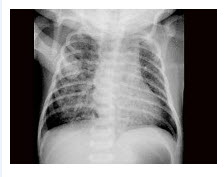

11、单项选择题

女婴,出现持续性呕吐,腹胀,如图所示,最可能的诊断为()

A.肠梗阻

B.肠扭转

C.肠闭锁

D.肠旋转不良

E.肠穿孔